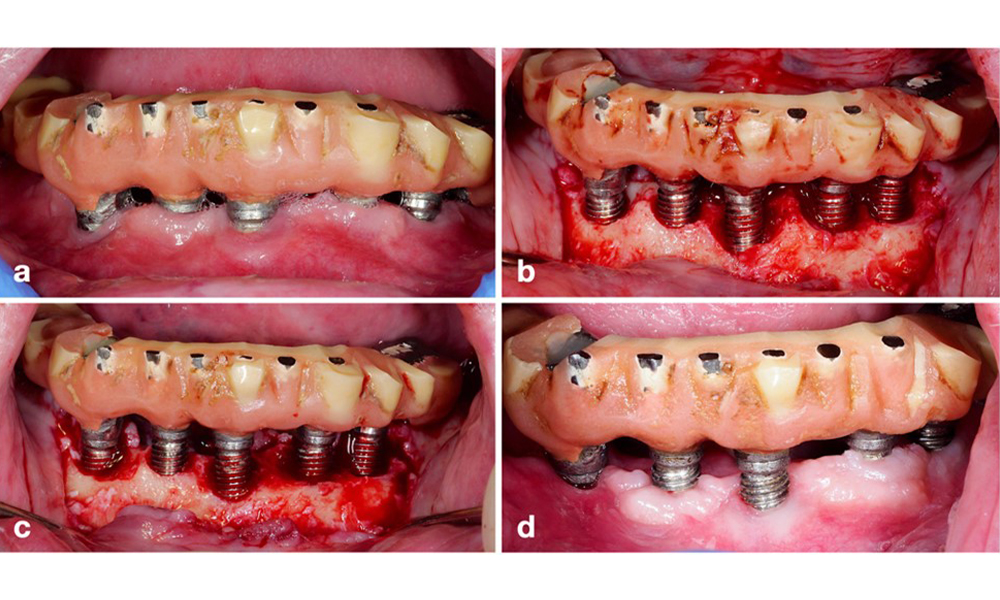

A resective approach (i.e., gingivectomy and/or apically positioned flap, with/without bone re-contouring) should be chosen in cases with mainly horizontal bone loss or wide defects, where the potential for bone regeneration is limited (figure 11).

Patient treated with a resective approach (a). After flap elevation mainly horizontal bone loss is seen (b), addressed by bone re-contouring (c) and an apically displaced flap resulting in a stable post-operative result (d).

Figure 11. Patient treated with a resective approach (a). After flap elevation mainly horizontal bone loss is seen (b), addressed by bone re-contouring (c) and an apically displaced flap resulting in a stable post-operative result (d).